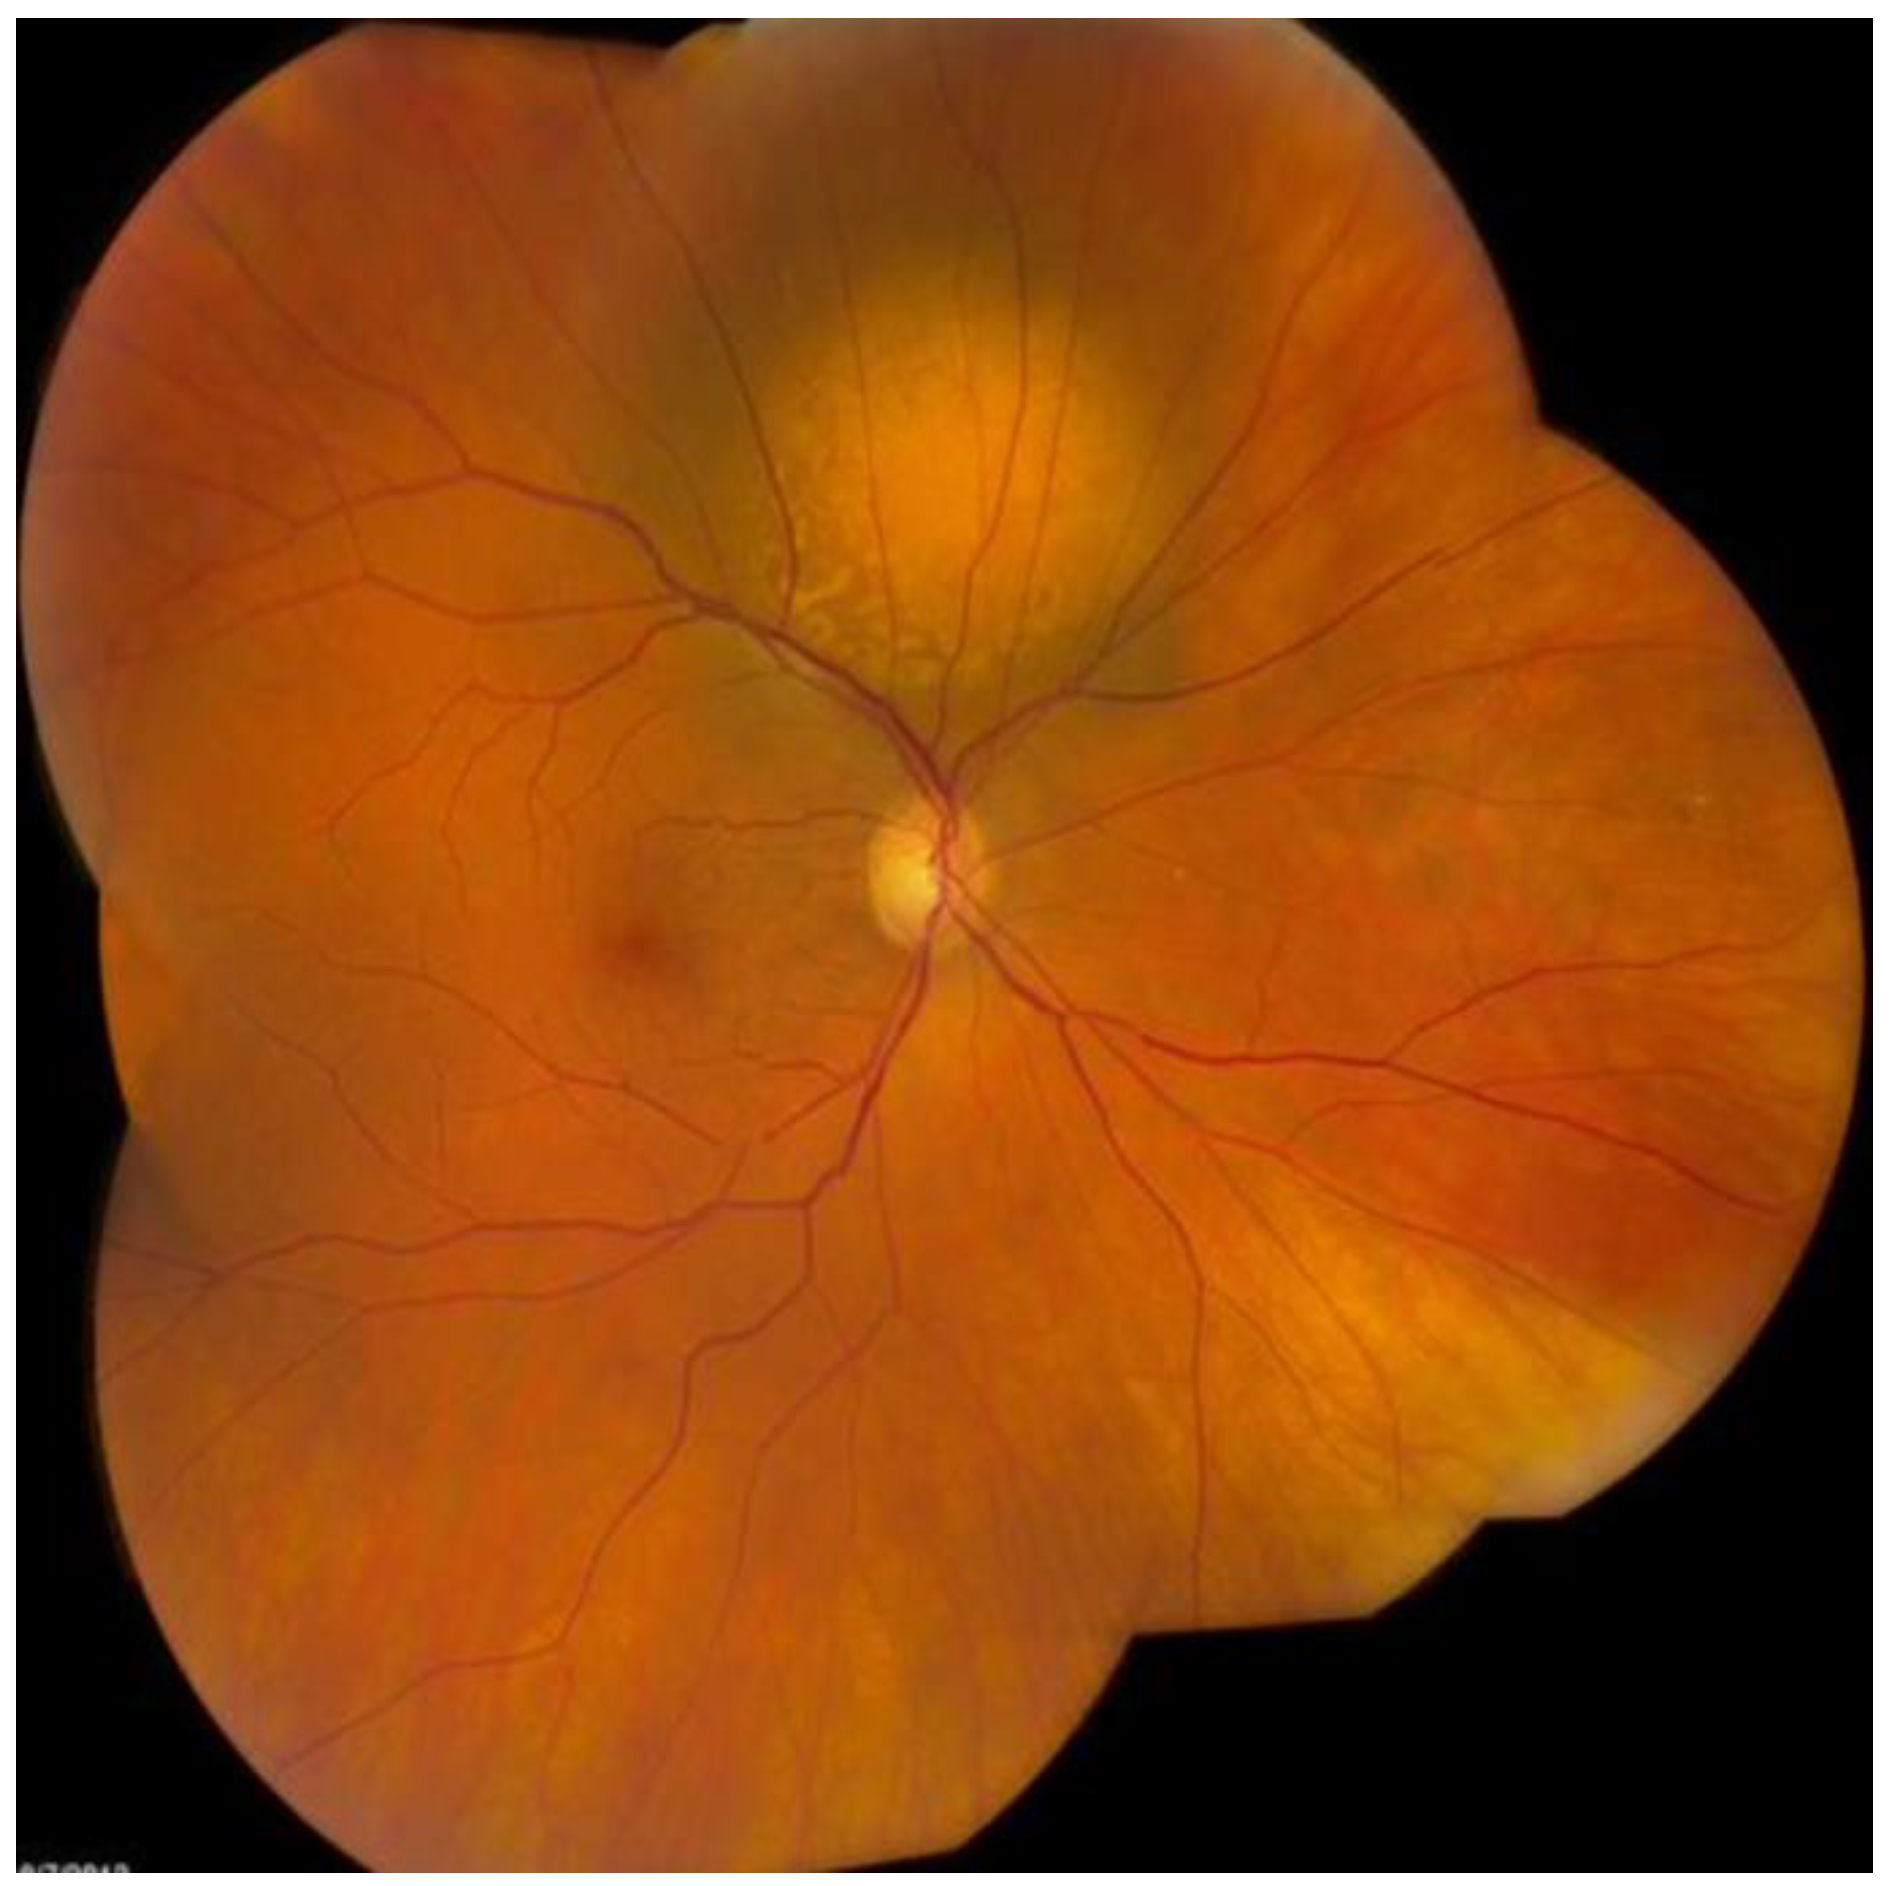

6. History

7. Physical Examination and Evaluation